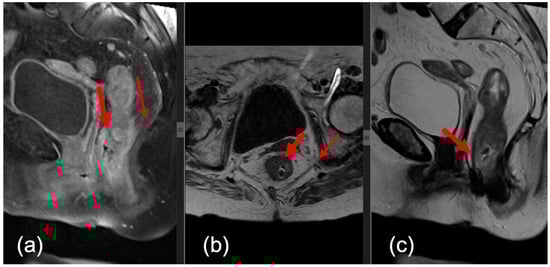

- Sagittal—this plane is used to locate the tumor and to plan the axial and coronal sequences;

- Axial—the plane is angled perpendicular to the tumor to correctly visualize the extension of the tumor against the rectal wall, as well as the distance between the tumor and the mesorectal fascia (MRF);

- Coronal—the plane is angled parallel to the axis of the tumor, which is perpendicular to the axial series.